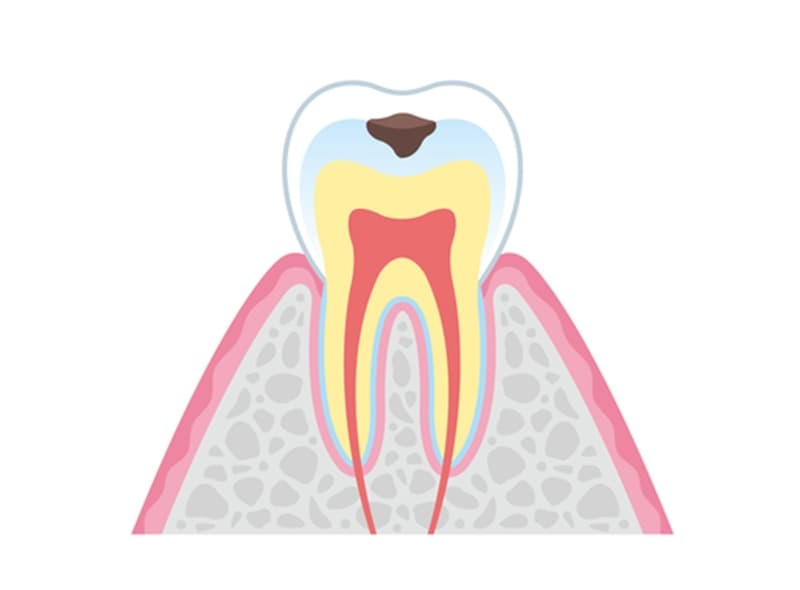

- C1

エナメル質のむし歯

むし歯がエナメル質に到達すると、歯の表面に小さな穴が形成されるのが特徴です。この段階では、感染歯質を除去し、適切な修復材料で歯を修復しなければなりません。症例によっては、経過観察を選択することもありますが、一般的には早期の介入が推奨されます。